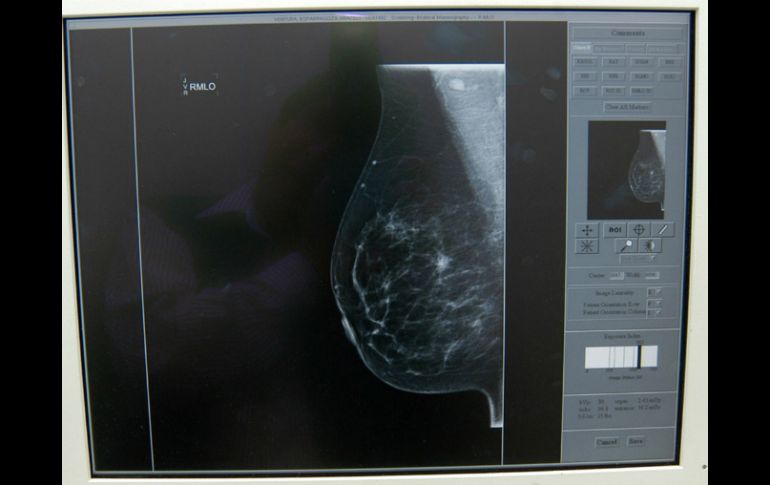

Tecnología | Es realizado por un equipo de científicos mexicanos del Tecnológico de Monterrey Diseñan dispositivo que detecta cáncer de mama a través de saliva Es realizado por un equipo de científicos mexicanos del Tecnológico de Monterrey Por: EFE 3 de abril de 2016 - 12:45 hs En México es predominante el número de decesos por una detección tardía de la enfermedad. NTX / ARCHIVO CIUDAD DE MÉXICO (03/ABR/2016).- La detección del cáncer de mama en una de sus etapas tempranas favorece su tratamiento, por lo que un equipo del Tecnológico de Monterrey (México) se encuentra desarrollando un dispositivo para facilitar este proceso a través de la saliva. A través del sensor incorporado en una película ultradelgada -de unos dos micras de espesor y diez milímetros de largo-, el dispositivo es capaz de detectar una proteína conocida como Cerb-b2. Esta proteína, que se localiza en la saliva, es desarrollada por "un grupo muy amplio de mujeres" que presentan cáncer de mama en las etapas iniciales, explica el responsable de la investigación, el doctor Joaquín Esteban Oseguera Peña. La gran ventaja de este método es que se adelanta a la detección que pueden realizar las mujeres con la autoexploración, ya que la prueba funciona cuando el tumor se mide en micras -con un tamaño mil veces menor al que tiene cuando se detecta manualmente-, "que es cuando es interesante detectarlo porque podría ser reversible". La Cerb-b2 llega a presentarse en, aproximadamente, un 98 % de las mujeres con cáncer de mama. Con este aparato "inmediatamente podría decidirse si hay esta proteína y, en consecuencia, las probabilidades grandes de que se esté desarrollando cáncer de mama", afirmó Oseguera, quien encabeza un grupo de investigación de ocho personas en el campus del Estado de México de la institución universitaria. "La idea fundamental -continúa el doctor- es que el dispositivo pueda ser accesible a todo el público, sobre todo en México en lugares alejados o de difícil acceso para equipos más sofisticados". Así, entornos de recursos limitados o de geografía complicada, como las sierras, podrían tener un indicador sencillo de si hay que emprender un tratamiento más sofisticado para tratar la enfermedad. En México, informa Oseguera, es "predominante" el número de decesos por una detección tardía. Aproximadamente una de cuatro mexicanas con cáncer sufren cáncer de seno, lo que causa a diario la muerte de quince mujeres, de acuerdo con los datos de la Agencia Internacional para la Investigación del Cáncer. Según el doctor, es "probable" que la idea de un dispositivo como este se pudiera extender a otros tipos de cáncer vinculados con otras proteínas, aunque se necesitaría "fundamentarlo con estudios". Por el momento, el equipo de investigación ha tomado contacto "solo a nivel preliminar" con algunos hospitales públicos del área, y en aproximadamente un año se habrá constituido todo el desarrollo adicional que permitirá realizar pruebas con pacientes. Temas Investigación científica Ciencia médica Mujeres Cáncer de mama Inventos Lee También “Vainilla”, esencia femenina que atrapa las miradas del FICM Pensión Mujeres Bienestar: Amplían la entrega de tarjetas hasta esta fecha NASA confirma si el cometa 31/ATLAS amenaza la vida en la Tierra o no Pensión Mujeres Bienestar: ¿Cómo es la entrega de tarjetas en Jalisco? Recibe las últimas noticias en tu e-mail Todo lo que necesitas saber para comenzar tu día Registrarse implica aceptar los Términos y Condiciones